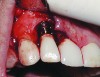

With all of the success seen in the dental community relative to implant placement, dentists are now seeing a more pronounced trend in dental implant care: an increase in the bacteriologic and/or traumatogenic occlusion-mediated loss of tissue integrity, accompanied many times by alveolar bone loss. The most common terminology applied to this condition is peri-implantitis (Figure 1). As replete as the dental literature is with success story after success story, there is virtually no detailed and specific prospective clinical trial data on the diagnosis and management of the peri-implant diseases, which result in soft tissue inflammation and the potential for alveolar bone destruction that may lead to the loss of the implant.

Fig 1. This implant was placed in March 2006. Peri-implantitis was clinically evident in April 2008, with bleeding on probing, suppuration, and increasing probing depth.

Figure 1